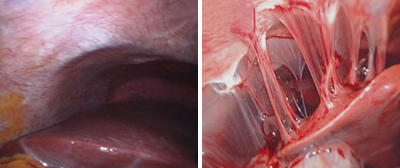

(1) 트리코모나스 질염

① 개요

트리코모나스 바지날리스라는 기생충에 의해 발생하는 감염입니다.

② 증상

- 악취 나는 황록색 거품 분비물

- 심한 가려움증

- 외음부 염증

- 배뇨통, 성교통